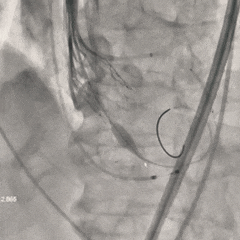

瓣膜第一次释放

初始定位造影时可见瓣架底端基本平齐猪尾导管(零位),瓣膜释放过程中瓣架出现下滑,至全展开位时瓣膜深度接近一个菱形格,位置过深,即刻回收瓣膜重新调整

重新调整后重新定位

考虑第一次释放时瓣膜位置偏深,第二次瓣膜定位调整至瓣架底端约为瓣上4-5mm左右